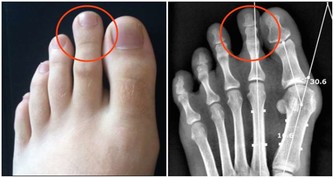

《黃帝內經》認為腎為“藏精之所,主骨生髓”,意即為生命的發動機,故古代醫家又稱腎為“先天之本”。腎藏精主生殖系統,如果生殖系統出現問題,比如說出現前列腺肥大,就說明腎的精氣不足了,要趕快補充精氣。老百姓常說“耳大有福”,背後的原理就是腎開竅於耳,腎氣充足則耳大飽滿、精力充沛,做事業自然拼勁十足、無往不利。曾國潘說“功名看氣宇,事業看精神”即是此意。經常耳鳴或者聽力下降的人,就是表明是腎氣不夠用了。什麼是腎主骨呢?中醫認為,人的骨骼強健與否,由腎精氣盈虧所決定。骨質疏鬆的人要補養腎的精氣,腎的精氣足了,骨骼就強健有力了。

人散步的時候會有很多生理反應,其中一個反應就是滿口生津。這代表你的腎氣、腎精得到補充了,因為在五行學說裡面唾液歸屬於腎水。所以腎陰虛的人口裡會經常乾,缺少唾液,這就是腎精不足了。那麼腎精氣不足會出現哪些症狀呢?常見的有腰膝酸軟、手腳冷、體虛乏力、耳鳴、脫髮、牙齒鬆動、骨質疏鬆、夜尿多、前列腺肥大、性功能減退、不孕不育、腎虧、更年期綜合症。